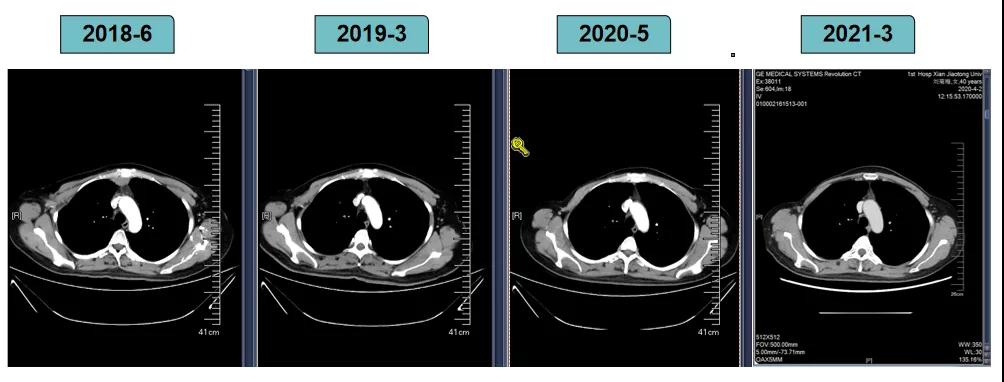

胸腹部增强CT示(2018-6-28):胸骨后占位,肝内异常强化灶,腹膜后肿大淋巴结。

靶病灶:腹主动脉左侧和下腔静脉右侧淋巴结

非靶病灶:肝左叶、肝右前叶下段;纵膈胸骨后淋巴结节;前上纵膈淋巴结;腹膜后小淋巴结

影像学评估-纵膈淋巴结: